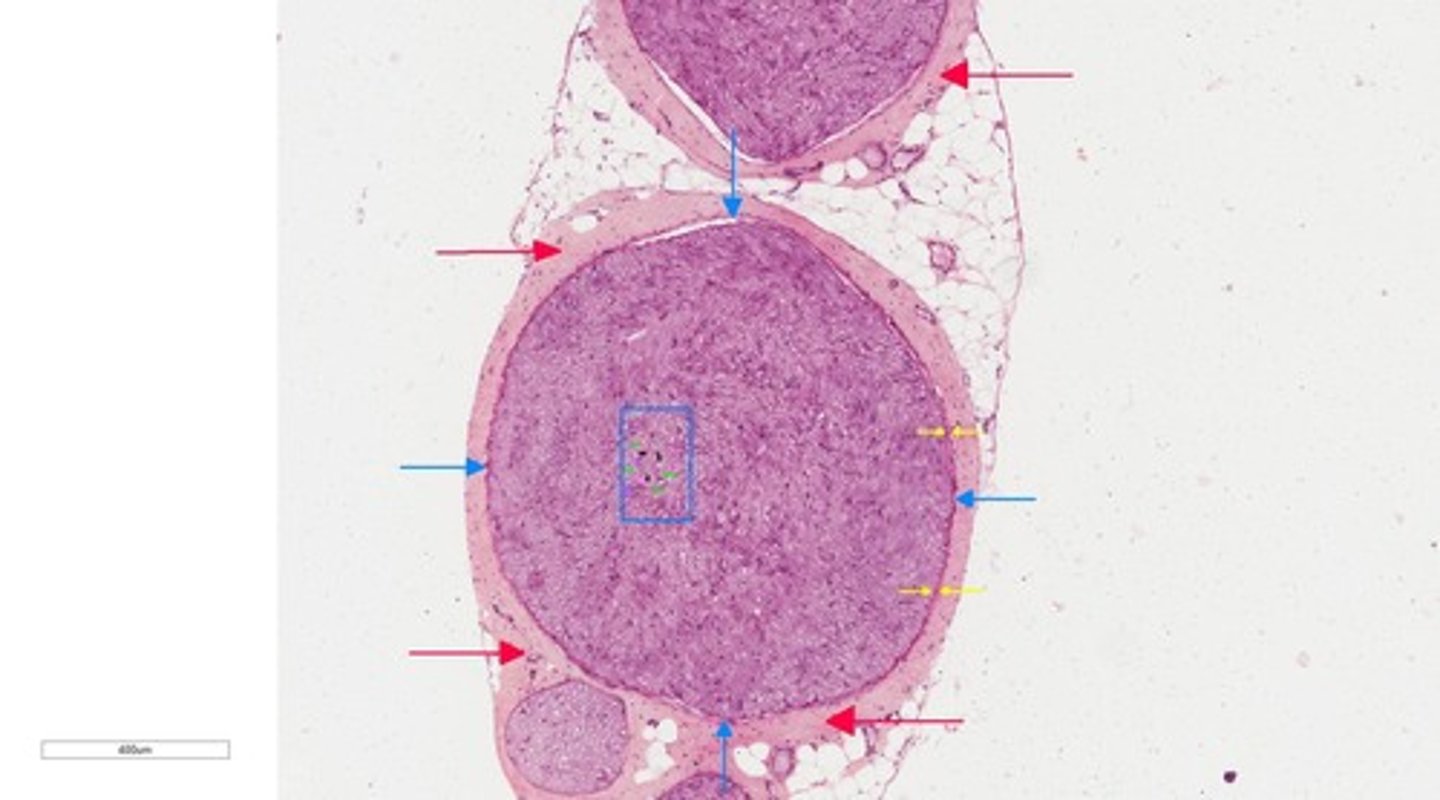

Epineurium

red arrow

fasicle

perineurium

blue arrow

Endoneurium

myelinated sheath

myelinated axon

myelin sheath gap

axon/myelinated axon

2

9

11

dendrite

3

neuroglia cell

4